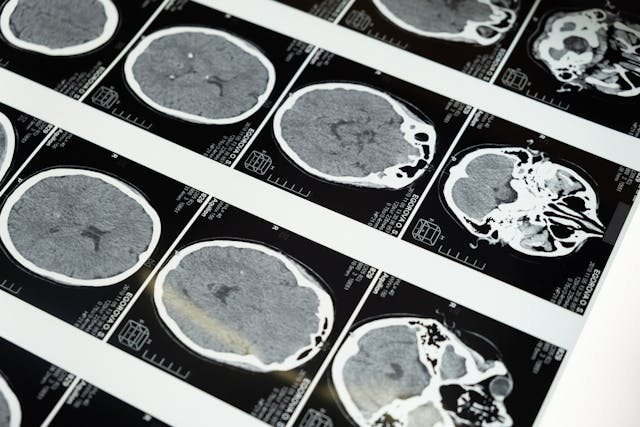

Do najczęściej wykonywanych operacji neurochirurgicznych zalicza się, między innymi zabiegi kręgosłupa, usunięcie guzów mózgu czy leczenie tętniaków. Poza interwencją chirurgiczną, istotna w powrocie do zdrowia jest również profesjonalna fizjoterapia. Dobrze sprawdzi się tutaj rehabilitacja domowa po operacjach neurochirurgicznych z dojazdem do domu pacjenta w Legionowie lub w okolicach. Skontaktuj się z FizjoActive, jeśli jesteś zainteresowany taką formą terapii.

- usunięciu guzów mózgu lub rdzenia kręgowego,

- neurochirurgicznych zabiegach tętniaków,

- urazach czaszkowo-mózgowych,